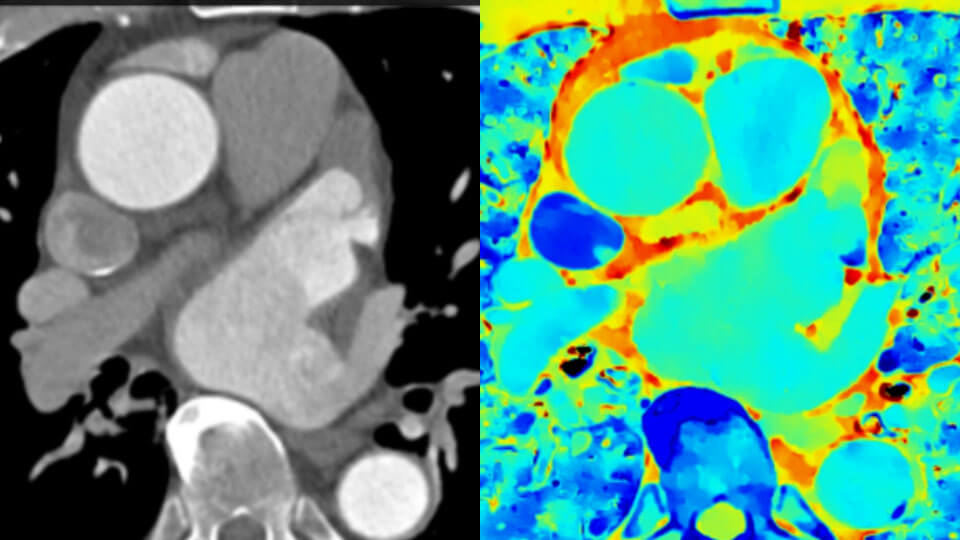

Simplemente mueva el control deslizante para comparar la TAC convencional con la TAC espectral basada en detectores.

Imagen de TAC convencional (izquierda) Imagen de TAC con detector espectral (derecha)

Ahora puede saber fácilmente tanto el "dónde están las cosas" del TAC convencional como el "lo que son las cosas" revelado por los datos del detector espectral. Las capas de datos espectrales enriquecidos mejoran la caracterización y la visualización del tejido, y reducen la necesidad de realizar exploraciones de seguimiento en exámenes subóptimos y hallazgos accidentales.